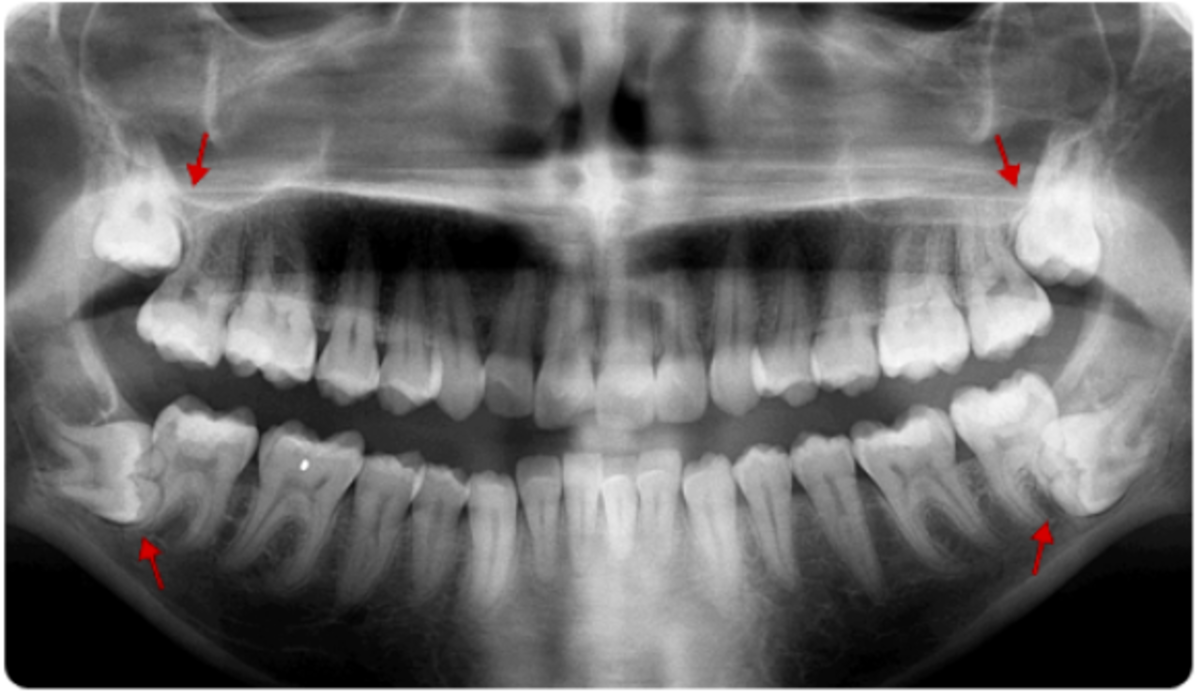

Οι φρονιμίτες ή επιστημονικώς τρίτοι γομφίοι είναι τα τελευταία δόντια της μόνιμης οδοντοφυΐας που αναπτύσσονται και εμφανίζονται στο στόμα...